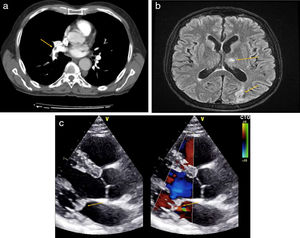

a) Angio-TC de arterias pulmonares. Defecto de repleción arterias del lóbulo inferior derecho e inferior izquierdo compatibles con TEP, flecha. b) RM cerebral en fase T2. Impactos isquémicos en hemisferios cerebelosos y en región occipital, flechas. c) Ecocardiograma en eje paraesternal largo. Insuficiencia mitral severa y masas endocárdicas sobre válvula mitral, indicado con flechas.

Presentamos el caso de un varón de 64 años de edad, exfumador de 20 paquetes-año desde hace 5 años, con antecedentes personales de vitíligo, en tratamiento con omeprazol 20mg. Consultó por disnea de inicio súbito, dolor torácico de características pleuríticas y síncope. En la exploración física se objetiva una saturación de O2 del 87% y taquicardia de 134 latidos por minuto. Destaca la presencia de un soplo sistólico i/vi en foco mitral, hepatomegalia no dolorosa de 3cm sobre el reborde costal y empastamiento en la extremidad inferior derecha. El hemograma demostró una anemia microcítica (hemoglobina 9,9g/dl), con ferritina de 1.728 ng/ml (valores normales [VN] 30-400 ng/ml). En la bioquímica destacaba una lactato deshidrogenasa de 814 U/l (VN: 125-250 U/l), la transaminasa glutámico pirúvica de 71 U/l (VN: 2-33 U/l), una proteína C reactiva 193mg/l (VN 0-5mg/l) y un dímero D>20.000 ng/ml. La angiografía por tomografía computarizada (angio-TC) demostró defectos de repleción en arterias del lóbulo inferior derecho e inferior izquierdo compatibles con TEP (fig. 1a). El Doppler venoso de miembros inferiores evidenció una TVP femoro-poplítea en la extremidad inferior derecha. Ante estos hallazgos, se ingresó al paciente y se inició tratamiento con enoxaparina ajustada por peso cada 12 h.

Setenta y dos horas más tarde, el paciente presentó pérdida de fuerza en la extremidad superior derecha y disminución del nivel de consciencia. La exploración neurológica puso de manifiesto la presencia de disminución de la fuerza proximal en el brazo derecho, acompañada de aumento de la base de sustentación y test de Romberg positivo. En la TC cerebral se observó la presencia de lesiones hipodensas, sin captación de contraste, en ambos hemisferios cerebelosos y el lóbulo occipital derecho. La resonancia magnética (RM) cerebral confirmó la presencia de lesiones isquémicas (fig. 1b). Ante la sospecha de cuadro embólico, se realizó un ecocardiograma transtorácico que objetivó una insuficiencia mitral severa y masas endocárdicas sobre válvula mitral, descartando la presencia de foramen oval permeable (fig. 1c). Los hemocultivos fueron repetidamente negativos, así como las serologías para Coxiella spp., Brucella spp., Bartonella spp. y Legionella spp.